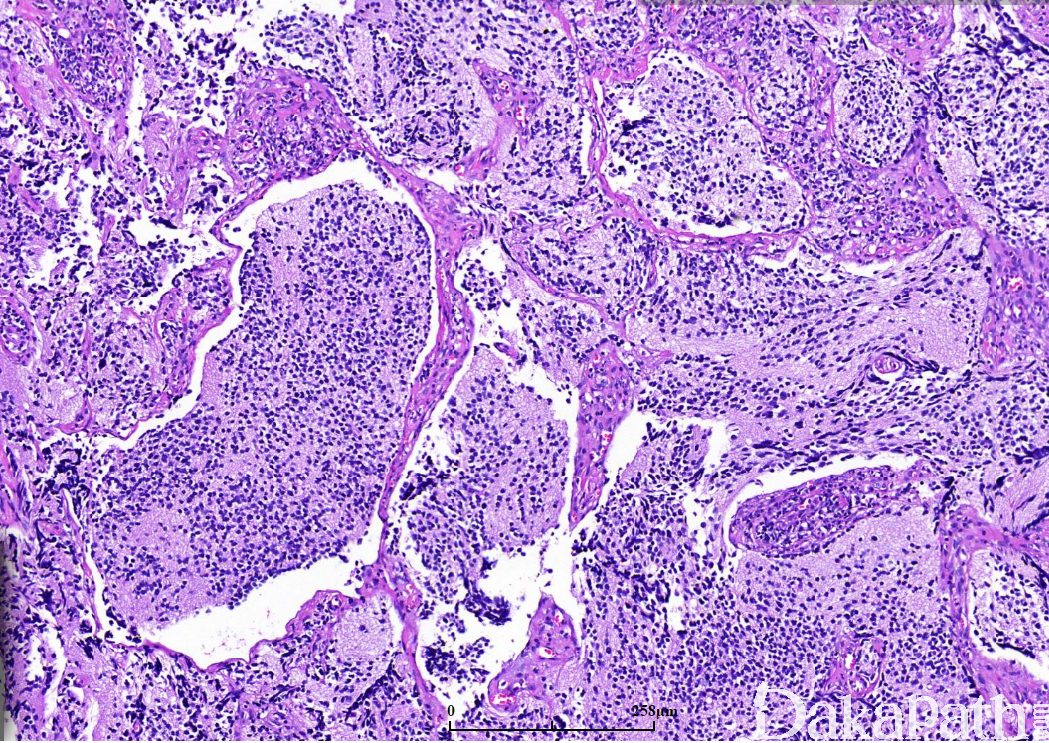

由巢状或小叶状分布的小至中等大神经母细胞所组成,巢或小叶之间为纤细的纤维血管性间隔;

在未分化型的神经母细胞形态学基础上,在局灶区域或明显可见神经纤维网(神经毡)和(或)Homer-Wright 菊形团(约 30%):1 层或数层神经母细胞围绕中央的神经毡性间质呈放射状排列;